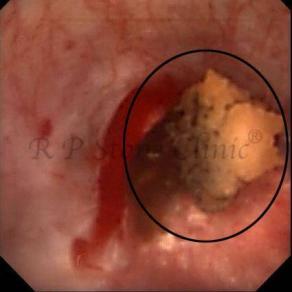

The Below Images Show Small Stones attached to the Renal Papillae.